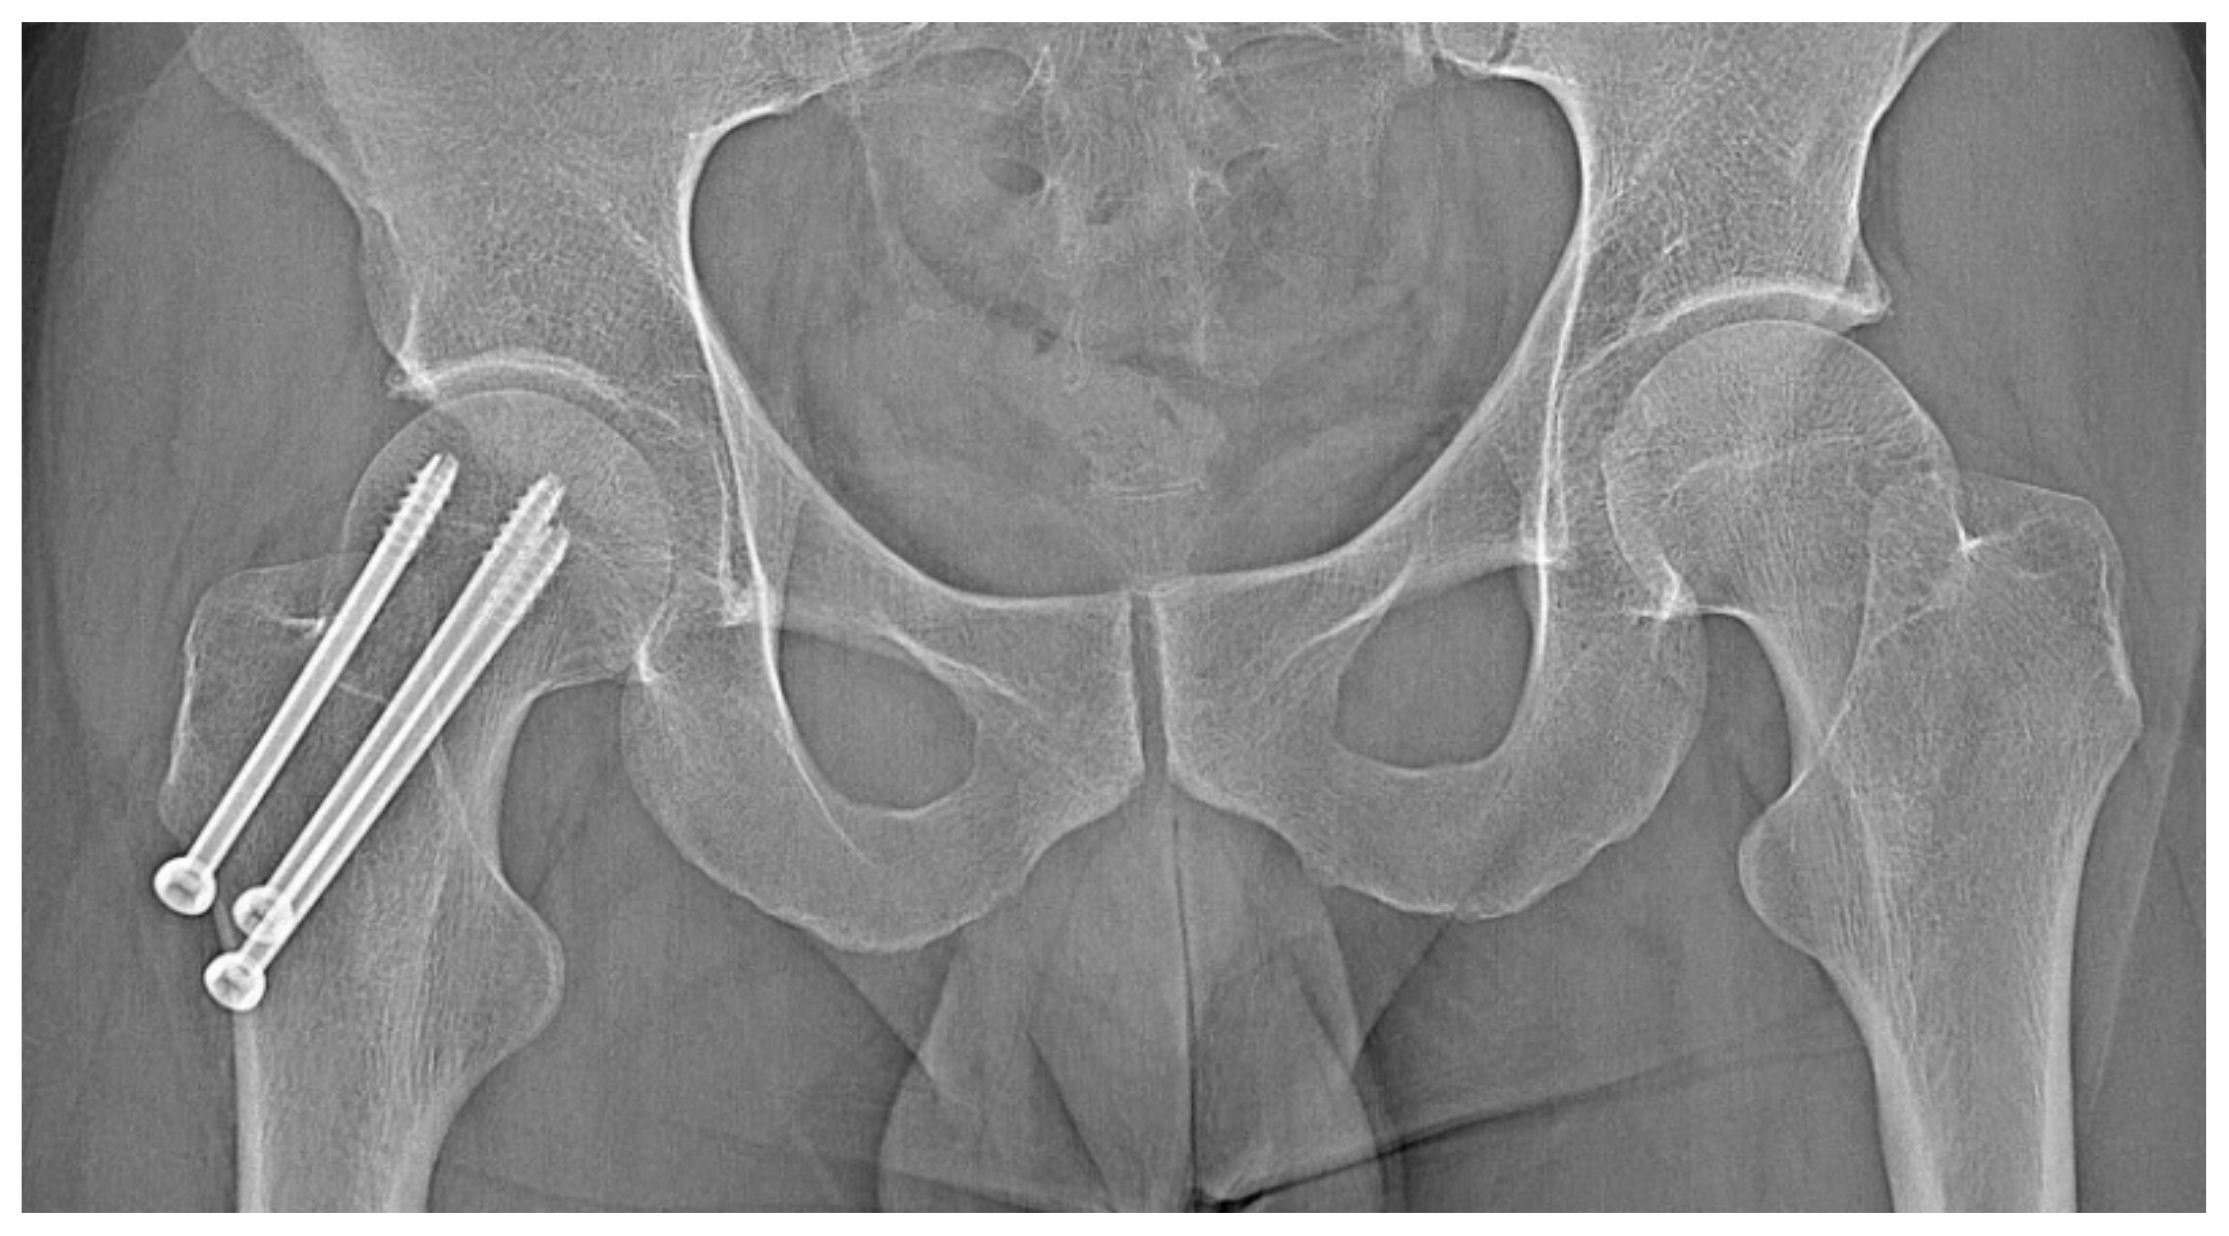

Figure 9.

X-ray view of internal stabilisation with three cannulated screws of the right femoral neck.

A 31-year-old male patient with post-exercise and night pain was seen at an orthopaedic outpatient clinic for diagnosis. The patient underwent a pelvic X-ray and an MRI scan of the right hip joint. The MRI description suggested a suspected fatigue fracture of the right femoral neck (Figure 8). The patient was qualified for surgery. Under general anaesthesia, internal stabilisation was made with three cannulated screws (Figure 9). During the following six months after surgery, the pain did not resolve. During further diagnosis, the patient had a CT scan of the hip joints. The examination revealed a focus of OO of 10 × 9 × 6 mm in the right femoral neck (Figure 10). The patient underwent thermoablation with intraoperative 3D navigation without complications (Figure 11). The VAS score of pain on the day of surgery was 7. Night and postoperative pain resolved completely. The VAS score on examination 3 months after surgery was 0. Cannulated screws were not removed.